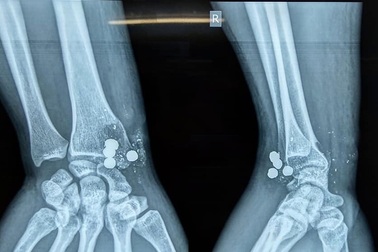

Nam thanh niên nghịch súng kíp, 5 viên đạn nổ găm vào cổ tayNam thanh niên đến nhà bạn chơi, thấy khẩu súng kíp gác trên mái nhà đưa xuống xem. Trong lúc nghịch súng, bất ngờ súng nổ, 5 viên đạn bắn thẳng vào cổ tay phải làm nam thanh niên bị thương.